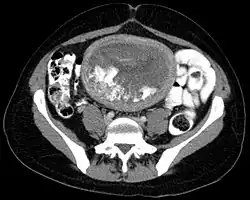

Hydatidiform mole on CT, axial view

The diagnosis is strongly suggested by ultrasound (sonogram), but definitive diagnosis requires histopathological examination. On ultrasound, the mole resembles a bunch of grapes ("cluster of grapes" or "honeycombed uterus" or "snow-storm").[14] There is increased trophoblast proliferation and enlarging of the chorionic villi, and angiogenesis in the trophoblasts is impaired.[15]